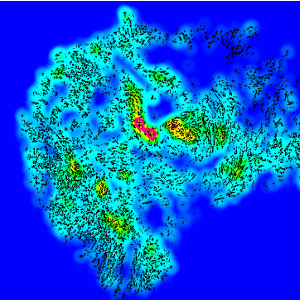

Figure 2

The results produced by the Hot Spot APP for the image in FIGURE 1. The user is presented with the created heatmap and the hot spot (red outline). In this case the hot spot was defined to follow the heatmap contours until the hot spot contained 200 nuclei. This definition can be changed for different use cases.